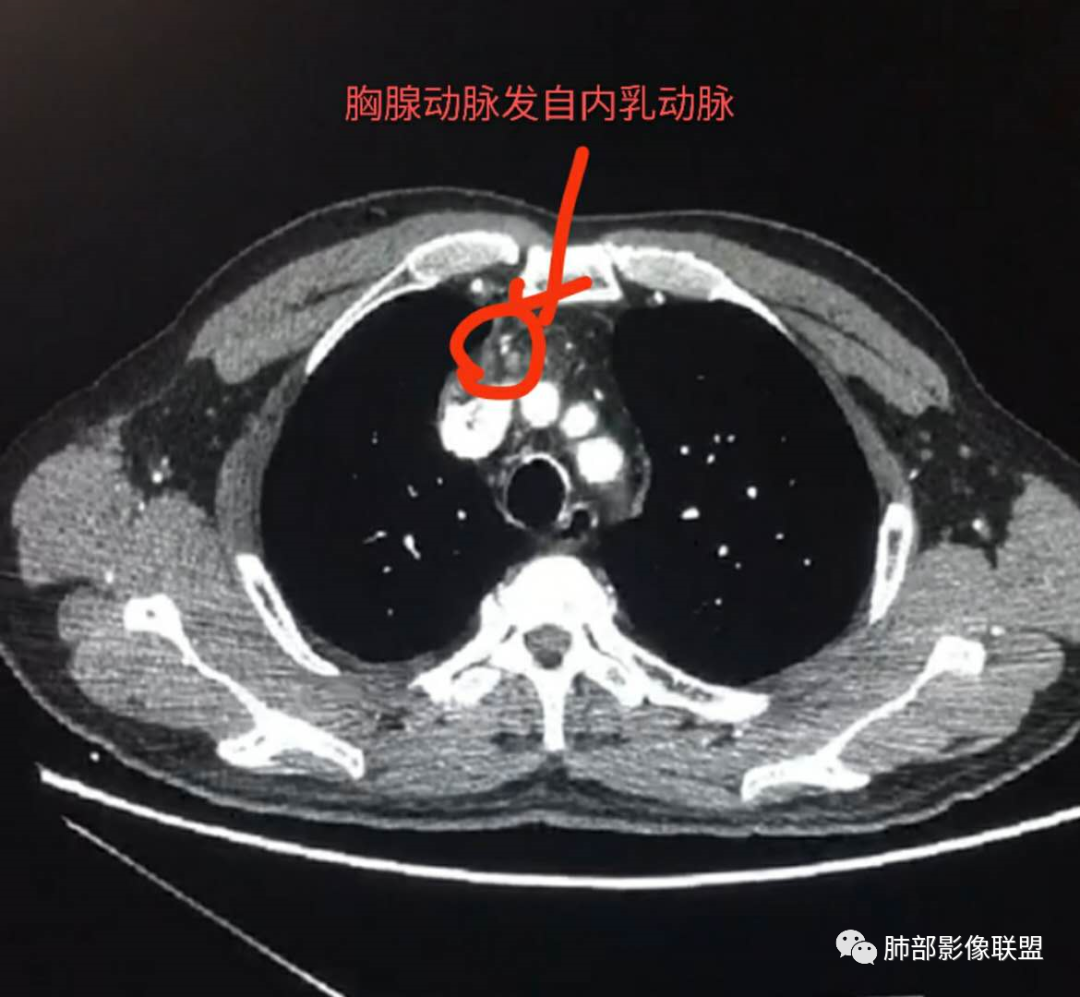

廖鹏飞:可疑胸腺动脉进入肿块

2.胸膜掀起,右侧内乳动脉略增粗,定位右前上纵隔内占位。